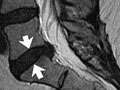

MRI of the spine

Normal:

The bones of the spine, discs, and nerves are normal.

No tumors, inflammation, or areas of nerve damage in the spine are present.

No disease or bone loss in the spine is present.

No ruptured discs are present. There are no structures pressing on a nerve.

No structural problems that have been present from birth (congenital problems) are found.

Abnormal:

Tumors, inflammation, or areas of nerve damage in the spine are present. A disease of the spinal cord, such as multiple sclerosis, is found.

Narrowing of the spinal canal (spinal stenosis) is present.

Broken bones or bone loss in the spine caused by injury or disease, such as arthritis, is found.

One or more discs of the spine are bulging or ruptured or pressing on a nerve.

A condition that has been present from birth (congenital condition) is found in the spine or the vertebrae.